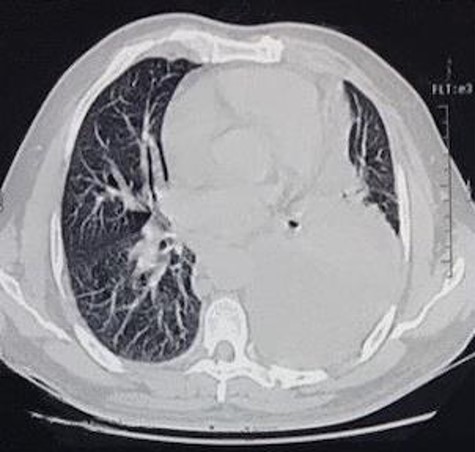

The second case consists of a 47-year-old male from a rural location in Guatemala that presented with malaise, fever, nausea, vomiting and left chest pain, described as oppressive that irradiates toward the neck. The pain got worse while being on supine position. The patient was previously treated with antibiotics and underwent a left thoracostomy due to a chest radiograph that showed a pleural effusion in the lung base (Fig. 3). On chest auscultation and percussion, air entry was reduced and dullness was perceived in the left lung base, respectively. Due to these findings, laboratory tests were ordered. The blood test showed an elevated lactate dehydrogenase at 156 U/L and the pleural fluid analysis showed an elevated lactate dehydrogenase at 1282 U/L, cholesterol level at 66 mg/dl, triglyceride level at 128 mg/dl, presence of Klebsiella pneumoniae and a hematoxylin stain positive for helminth larvae. According to these results, the pleural effusion was classified as an exudate. The high triglyceride level was consistent with a chylous effusion. A chest CT showed left loculated pleural effusion, cardiomegaly, slight pericardial effusion and mediastinal adenomegaly (Fig. 4). The patient presented full recovery after surgical and medical treatment.

CT scan axial view of left pleural effusion, cardiomegaly and pericardial effusion.